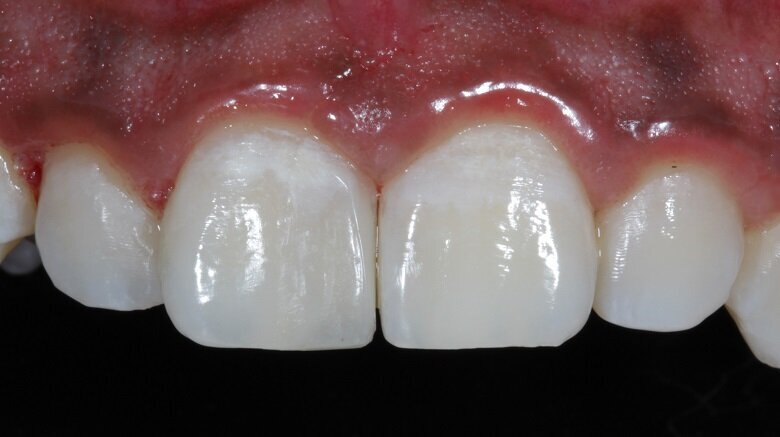

A 21 year old male reported to the clinic with a chief complaint that he was unhappy with his smile as he had a gap in between his front two teeth. He wanted a quick fix and had high aesthetic demands. Pre-operative photographs were taken at this point (Fig 1). On examination, tooth 11 showed decay mesially all the way extending upto the incisal edge (Class IV cavity). Tooth 21 also showed mesial decay only from the palatal aspect (Class III cavity).

Fig 1: Pre-operative photograph